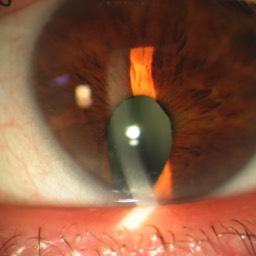

Quelques pathologies ophtalmologiques du segment antérieur